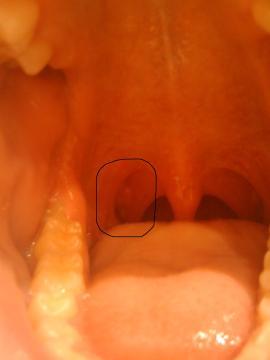

Pro větší náhled klikněte na obrázek

Dobrý den, před cca měsícem jsem si všimnul nad pravou mandlí (na zadním oblouku jí ohraničující) 2-3 růžových útvarů podoby rýže. Nijak to nebolí, ale také nemizí (nad levou mandlí podobné a menší útvary zmizely). Chtěl bych se Vás zeptat zda může jít o nějakou bakteriální infekci? Před cca měsícem a půl jsem měl opakovaně zvýšené hodnoty štítné žlázy (T4) ale TSH v normě, po měsíci se stav hormonů spontánně upravil, výsledek pravděpodobně prodělaný zánět štítné žlázy. Děkuji Vám mnohokrát za odpověď.

Pravděpodobně se jedná o čepy na mandlích, které se objevují v souvislosti se záněty mandlí. Doporučím Vám navštívit ORL lékaře.